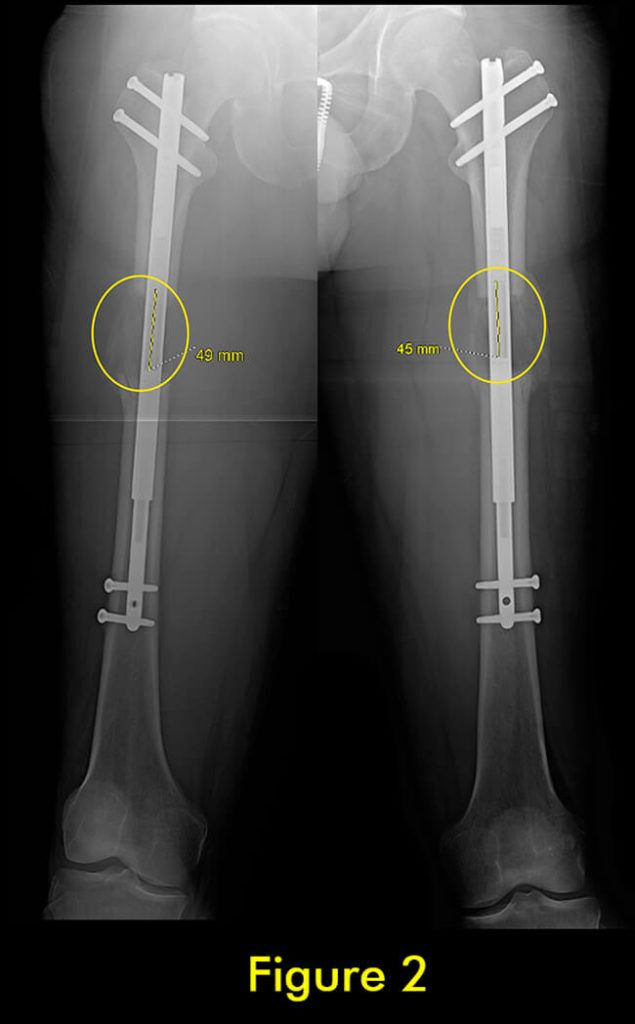

过早合并示意图1

图1:延长量细微差异

过早合并示意图2

图2:X光片确认诊断

过早合并示意图3

图3:重复截骨术

过早合并示意图4

图4:完全巩固